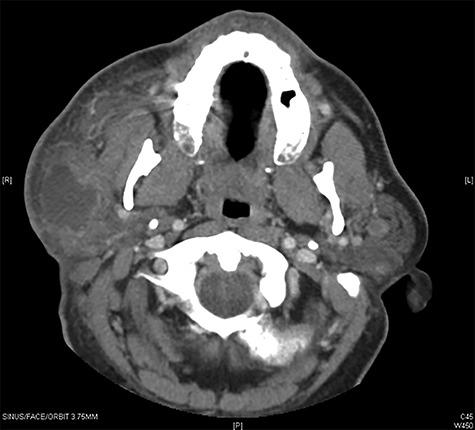

A benign lymphoepithelial cyst (BLEC) is defined as a rare, benign lesion composed of single or multiple cysts found within salivary glands or the lateral cervical area. Increasing reports suggest an association between BLEC and human immunodeficiency virus (HIV), although its pathogenesis remains unclear. We report a 51-year-old male who presented with recurrent bilateral BLECs after initial parotidectomy of cyst. An HIV panel was then performed with a positive result. We review the surgical and medical managements of BLEC while also discussing further treatment recommendations. Clinicians should be aware that BLEC recurrence postparotidectomy may be the initial presenting symptom of HIV in a patient with no risk factors.

良性淋巴上皮囊肿(BLEC)被定义为一种罕见的良性病变,由唾液腺或颈外侧区域内发现的单个或多个囊肿组成。越来越多的报告表明BLEC与人类免疫缺陷病毒(HIV)之间存在关联,尽管其发病机制尚不清楚。我们报告了一名51岁男性,他在初次腮腺囊肿切除术后出现双侧BLEC复发。随后进行了HIV检测,结果呈阳性。我们回顾了BLEC的手术和药物治疗,同时也讨论了进一步的治疗建议。临床医生应意识到,在没有危险因素的患者中,腮腺切除术后BLEC复发可能是HIV的初始表现症状。